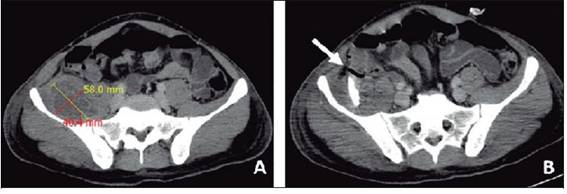

Al paciente se le diagnosticó piomiositis de músculo iliopsoas mediante una tomografía computarizada, la cual evidenció una importante cantidad de material purulento, que se drenó mediante punción percutánea y colocación de dreno (Figura 1). Los hemocultivos y el cultivo del contenido del absceso resultaron positivos por un Staphylococcus aureus meticilinosensible, con resistencia inducible a clindamicina negativa.